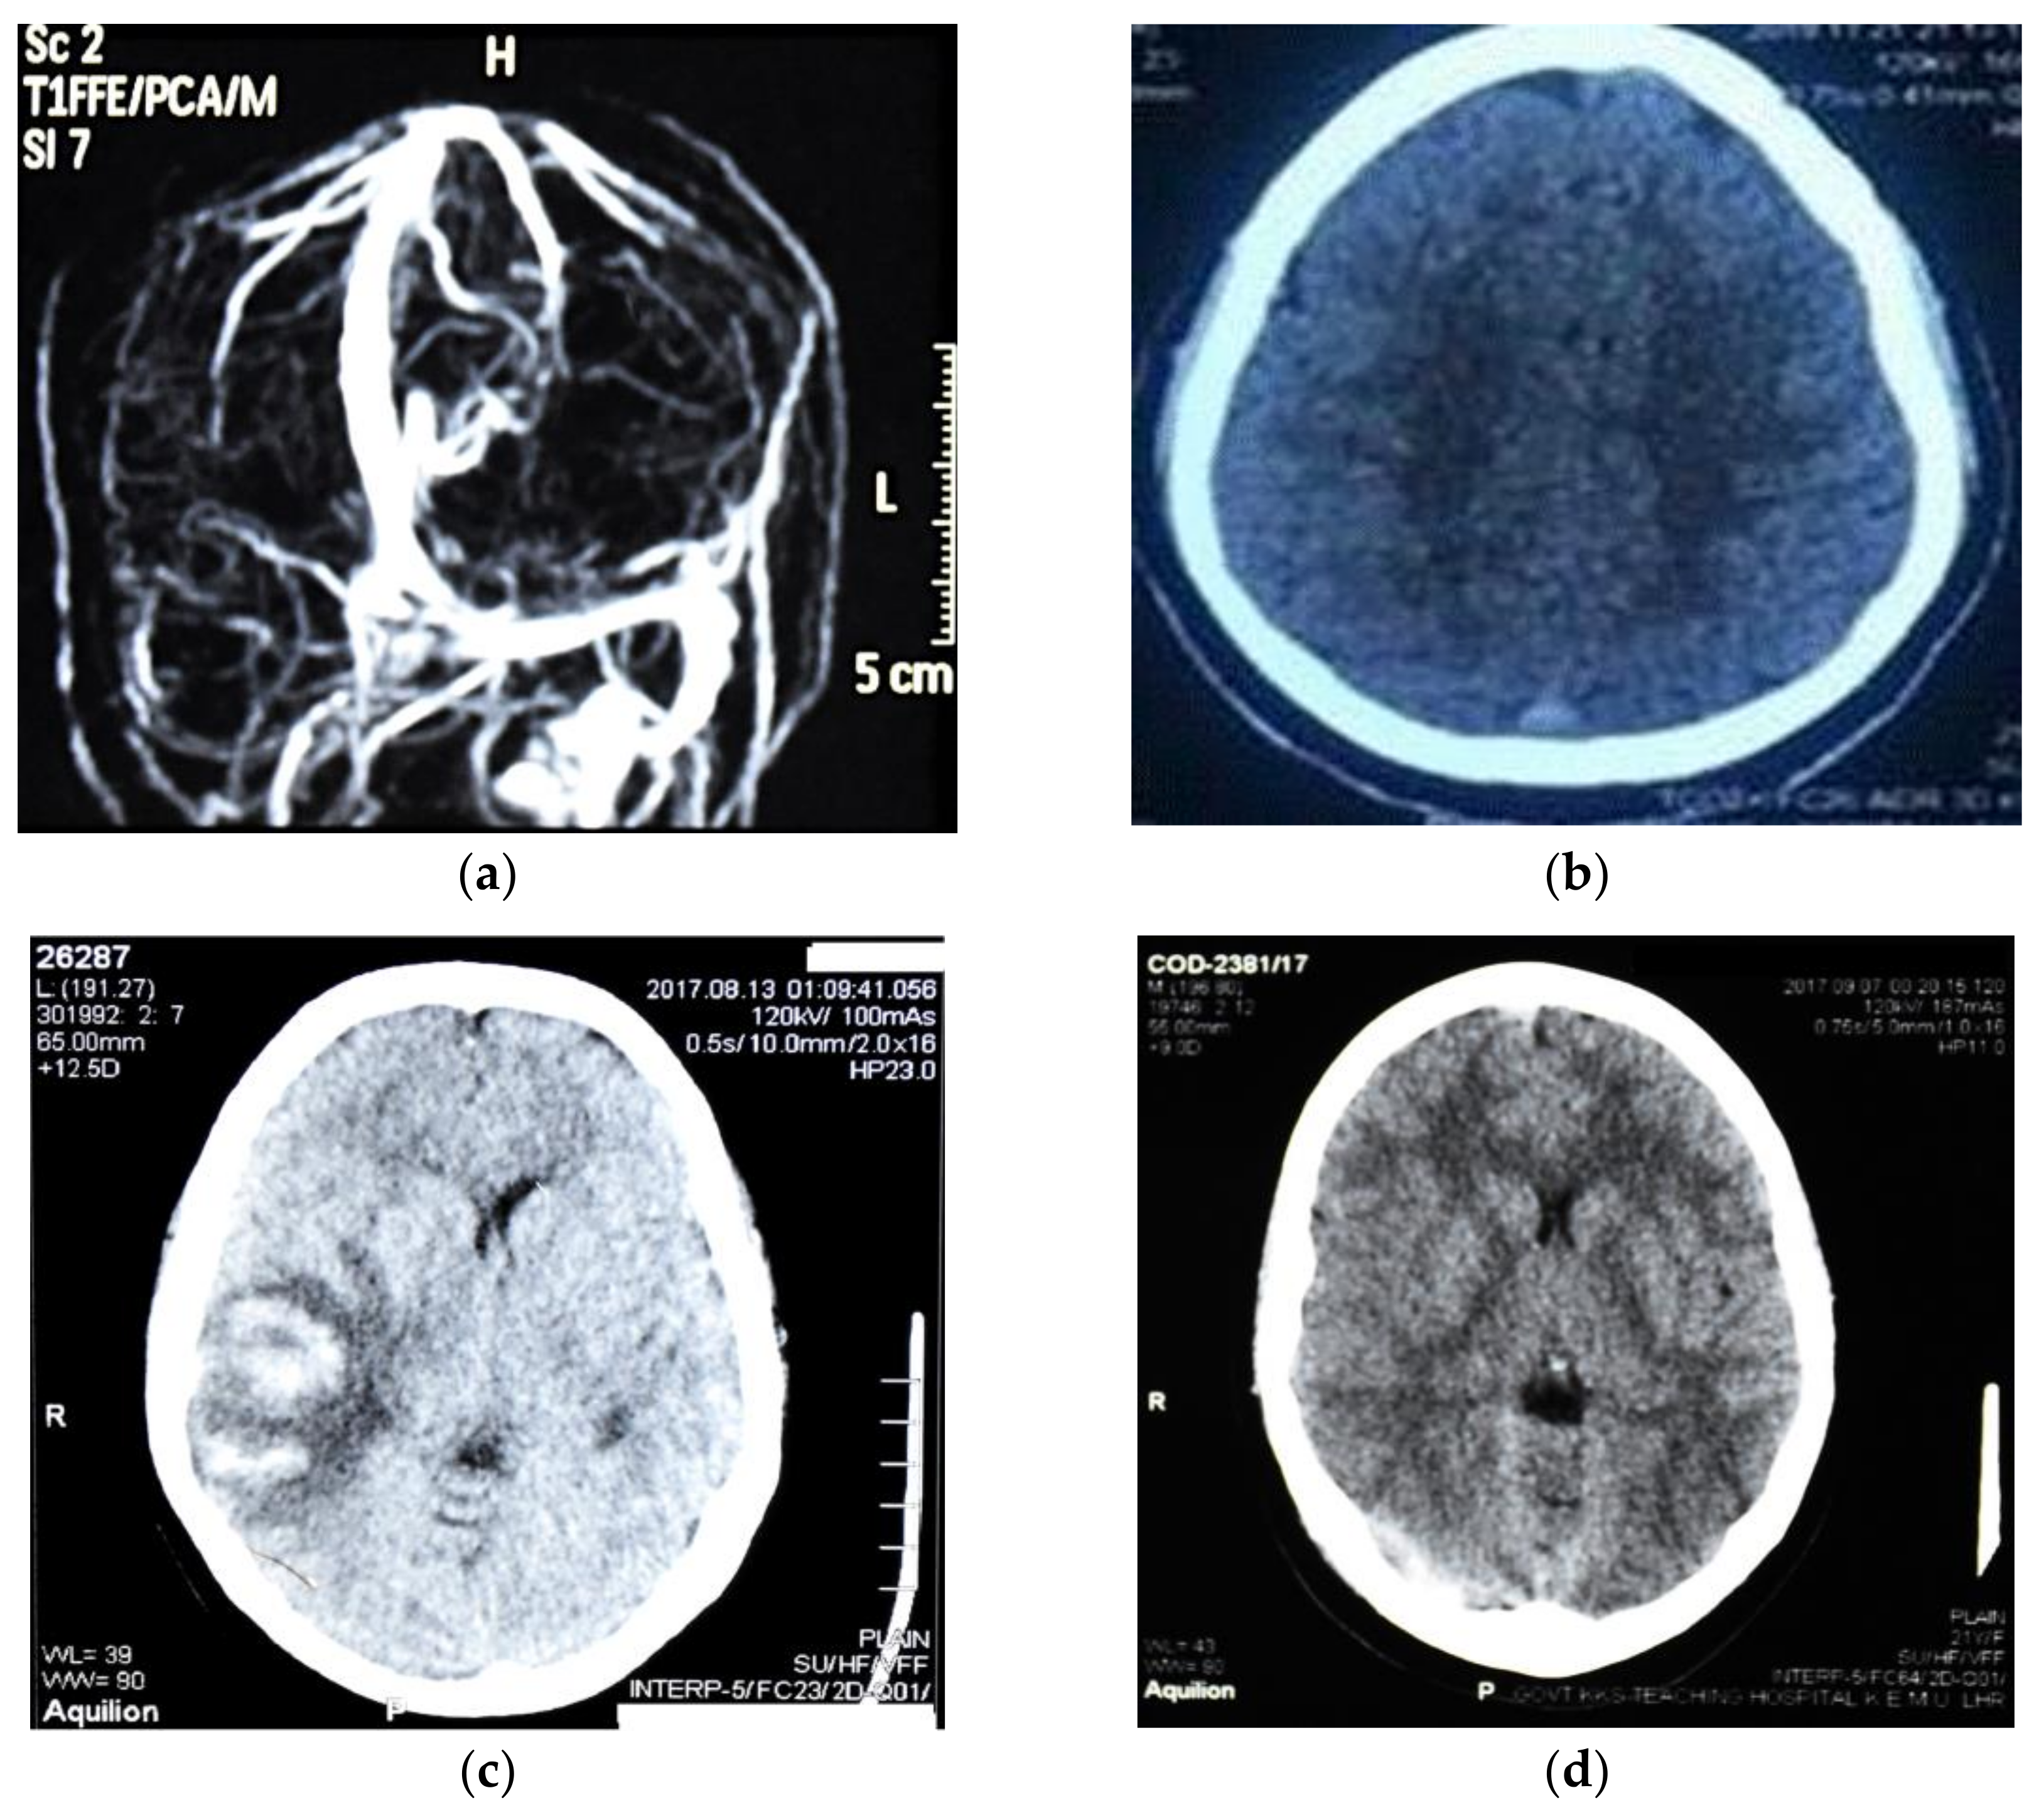

2.4. Magnetic Resonance Imaging (MRI) and Magnetic Resonance Venography (MRV)

3.3. Neuroradiological Findings